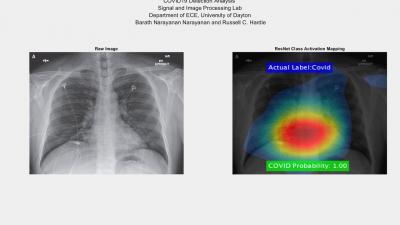

अमेरिकेच्या एका वैज्ञानिकाने एका सॉफ्टवेअरचा शोध लावला असून या सॉफ्टवेअरच्या मदतीने फक्त काही सेकंदात शरीरात लपून असणाऱ्या कोरोना व्हायरसची माहिती मिळणार असल्याचा दावा केला आहे.

बराथ नारायणन असं युनिव्हर्सिटी ऑफ डेटॉन रिसर्च इन्स्टिट्यूटच्या वैज्ञानिकाचं नाव असून त्यांनी शरीरात कोरोना असल्यास त्याचा शोध लावणारं एक सॉफ्टवेअर तयार केलं आहे.

सॉफ्टवेअर कोड व्यक्तीची छाती स्कॅन करून शरीरात लपून बसलेल्या कोरोनाचा शोध घेऊ शकतं असा दावा नारायणन यांनी केला आहे.

शरीरात लपून बसलेल्या कोरोना व्हायरसबाबत सॉफ्टवेअर 98 टक्के बरोबर माहिती देण्यासाठी सक्षम असल्याचं देखील वैज्ञानिकाने म्हटलं आहे.

कोरोनासाठी तयार करण्यात आलेले हे खास सॉफ्टवेअर सामान्य एक्स रे स्कॅनिंग मशीनपेक्षा एकदम वेगळं आहे. आर्टिफिशिल इंटेलिजन्सच्या मदतीनेच तयार करण्यात आले आहे.